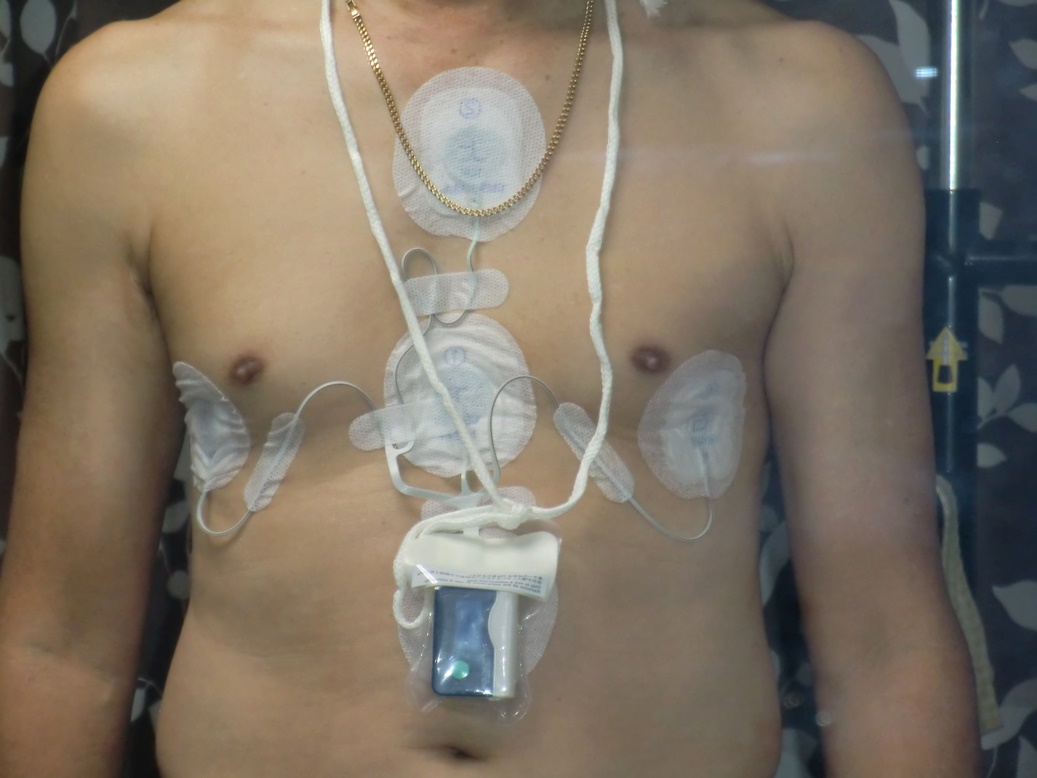

24時間測定の心電図です。

今日は心臓の定期検査の一部として、24時間心電図計を取り付けに行きました。

今の掛かり付けの医師からの紹介で、最初に診てもらっていた病院に行った訳ですが、今日はこ

の心電図を取り付けるだけと聞いていたので、すぐに終わるものと思っていたところ、20日に受

ける予定の心エコーと、腹部エコーまでしますというのでこの病院の連絡の悪さに爆発してしま

いました。

結局病院側の言い分をねじ伏せて、心電図の取り付けだけになりましたが、今度はその前にふつ

うの心電図をとると言いだしまたここで一悶着です、ここでも自分の言い分を通し機械の取り付

けだけにしてもらいました。

最後に診察費を払って帰るのですが、これを取り付けるだけで5.350円でした思わず内訳を聞いて

帰りましたが、家に帰ってからもイライラが治まりませんでした。